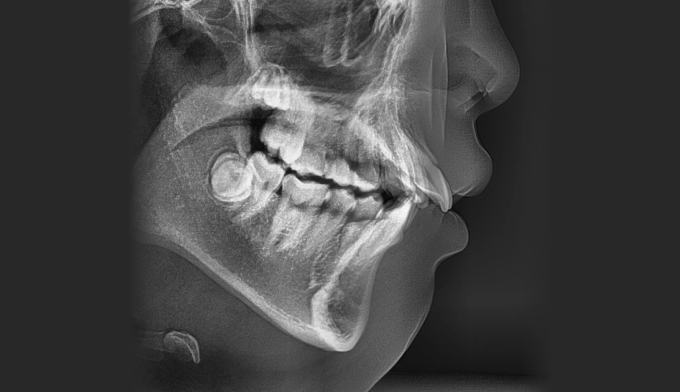

앞니가 돌출되어 있으면서 동시에 위 맨끝 어금니가 아래 어금니와 사선으로 물려있는 가위교합이 관찰됩니다.

가위교합은 음식물 섭취에 있어서도 비효율적이지만, 올바른 잇솔질을 하기가 어려워 구강위생에도 좋지 않아 교정이 필요합니다.

돌출입을 해소하고 동시에 가지런하지 못한 치열을 바르게 펴서 양치하기 좋은 상태로 만들어줍니다.

총 교정기간은 23개월입니다.